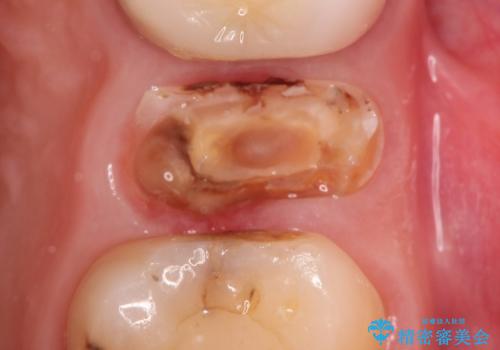

ワイヤー治療では非常に困難な、著しい前歯の傾斜を伴う過蓋咬合ですが、マウスピースにより割と短期間で状態を改善することができます。